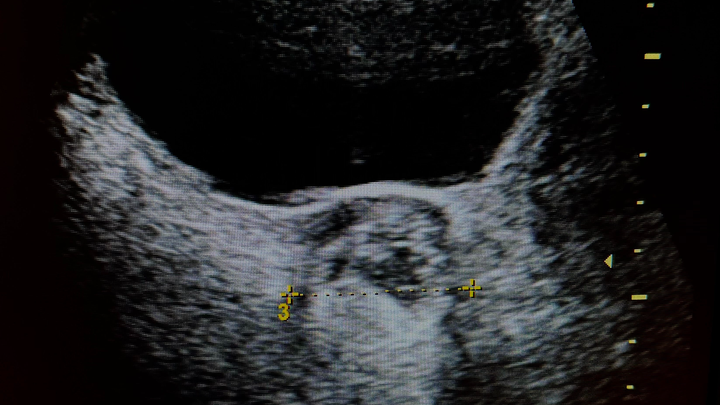

I am in need of a laparoscopic surgery to remove a Dermoid Cyst on my left ovary that I have had since 2024. Normally, most cysts can resolve on their own, but because there is tissue in this cyst, it will not resolve on its own and will only continue to grow. I am at the point of having slight pain/discomfort, and if I do not have surgery to remove it, it will eventually lead to ovarian torsion and can cause me to lose my ovary if left untreated. As someone who hopes to have children someday, it is very important I get this surgically removed sooner rather than later, as it has already been a year and a half of it growing. Even with insurance, I am looking at a high medical bill. Any help towards this surgery is appreciated.